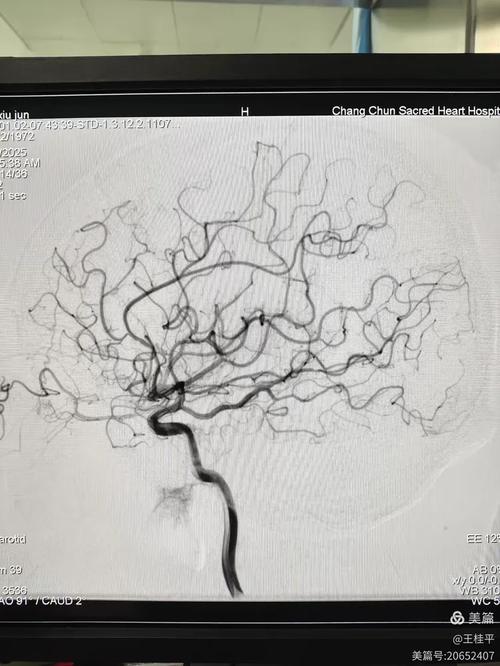

评估病情严重程度和预后

- 评估侧支循环: 这是CTA的另一个巨大优势,当主血管堵塞后,大脑会启动自身的“备用通道”(侧支循环)来代偿,CTA能清晰地显示这些侧支循环是否建立、是否良好。侧支循环越好,意味着缺血区域的脑组织能获得更多的“替代”血液,脑坏死的范围就越小,患者的神经功能缺损就越轻,预后也越好。